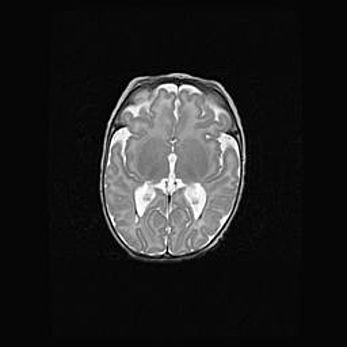

Наружная гидроцефалия с возможной атрофией височных областей.

Возраст: 28 дней

Вес: 3670 г

Пол: мужской

Окружность головы: 38 см

Срок гестации: 40 недель

Гидроцефалия головного мозга у новорожденных – это заболевание, которое характеризуется скоплением избыточного количества спинномозговой жидкости в желудочковой системе головного мозга в результате затруднения её перемещения от места выработки к месту поглощения в кровеносную систему или вследствие нарушения абсорбции. При открытой наружной форме гидроцефалии у новорожденных расширяются и переполняются субарахноидные пространства.

При нормотензивных  формах,  которые,  как  правило,  являются  следствием  перенесенных ишемических  повреждений  паренхимы  мозга,  возможно  сочетание микроцефалии  с нормотензивной гидроцефалией. В основе данных изменений лежит атрофия больших полушарий с преимущественной  локализацией  в  лобно-височных  областях.